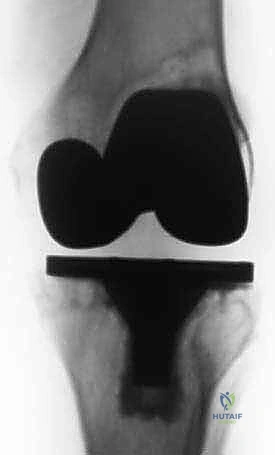

جراحة مراجعة مفصل الركبة الكلي: التغلب على فقدان عظم الفخذ باستخدام الدعامات والطعوم العظمية

جراحة مراجعة مفصل الركبة الكلي هي إجراء متخصص يُعالج فشل المفصل الصناعي السابق وفقدان العظم، خاصة في عظم الفخذ. يتضمن العلاج استخدام دعامات معدنية أو طعوم عظمية لاستعادة بنية المفصل ووظيفته، ويُعد الأستاذ الدكتور محمد هطيف الرائد في هذا المجال بصنعاء.

الخلاصة الطبية السريعة: جراحة مراجعة مفصل الركبة الكلي (Revision Total Knee Arthroplasty) هي إجراء جراحي معقد ومتخصص للغاية، يهدف إلى علاج فشل المفصل الصناعي السابق والتغلب على التحديات التشريحية الناتجة عن فقدان العظم، وتحديداً في عظم الفخذ (Femur). يتطلب هذا الإجراء استخدام تقنيات متقدمة مثل الدعامات المعدنية المعيارية (Modular Augments)، المخاريط (Cones)، والطعوم العظمية (Bone Grafts) لاستعادة بنية المفصل، خط المفصل الطبيعي، والميكانيكا الحيوية للركبة.

1. الدعامات المعدنية المعيارية (Modular Metal Augments)

تُستخدم في حالات فقدان العظم من النوع الثاني (AORI Type 2). وهي عبارة عن كتل معدنية (غالباً من التيتانيوم) تأتي بأحجام وسماكات مختلفة (5 ملم، 10 ملم، 15 ملم). يتم تثبيتها بمسامير أو أسمنت عظمي في الجزء الخلفي أو السفلي من المفصل الصناعي لتعويض الفجوات العظمية واستعادة خط المفصل بدقة.

2. المخاريط والأكمام الميتافيزيقية (Metaphyseal Cones and Sleeves)

هذه هي التقنية الأكثر تطوراً لحالات فقدان العظم الشديد (AORI Type 3). تُصنع هذه المخاريط من معادن مسامية عالية التكنولوجيا مثل "التانتالوم" (Trabecular Metal) أو التيتانيوم المسامي ثلاثي الأبعاد.

كيف تعمل؟ هذه المواد تحاكي بنية العظم الإسفنجي البشري. عند زرعها في الفجوة العظمية، ينمو العظم الطبيعي للمريض داخل مسام هذه المخاريط (Biological Ingrowth)، مما يوفر ثباتاً بيولوجياً مذهلاً طويل الأمد لا يمكن للأسمنت العظمي توفيره.